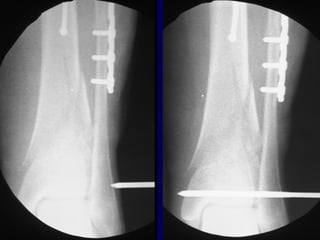

• 63.

Reduction of DistalTibial Fractures • Distractor • Joy Stick • Fibular Plating • Calcaneal Traction

• 70.

• 79.

• 85.

Proximal and DistalCases Courtesy of R. Winquist M.D. Seattle, Wa.